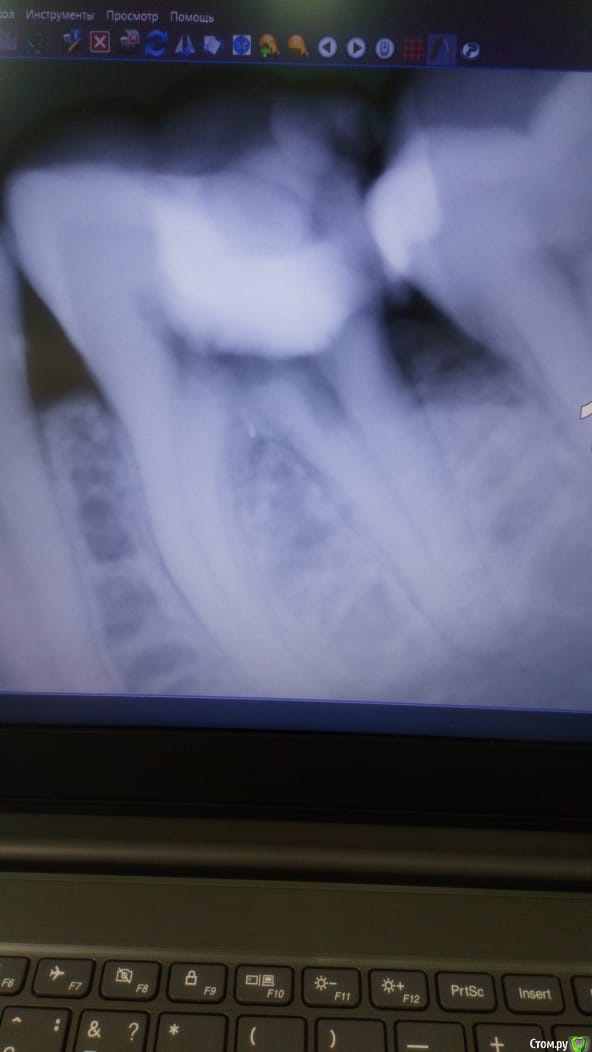

Dassety Опубликовано 10 марта, 2020 Автор Поделиться Опубликовано 10 марта, 2020 Зуб, 5-ка (большой жевательный слева снизу). Снимки прилагаю до склеивания и после. Ссылка на комментарий

Dassety Опубликовано 11 марта, 2020 Автор Поделиться Опубликовано 11 марта, 2020 а покажите плз снимок до вмешательства врача.Она, мне его, к сожалению, теперь не дает. Говорит что вот эти были первые. Хотя я точно помню, что изначально видела у нее другой снимок. Вот во вложении, как она утверждает, первонаяальные снимки Ссылка на комментарий